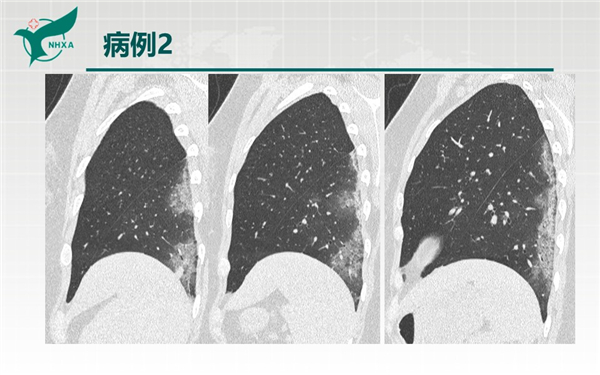

【病例分享】新型冠狀病毒肺炎3例(西安市第九醫(yī)院)

幻燈片2.jpg